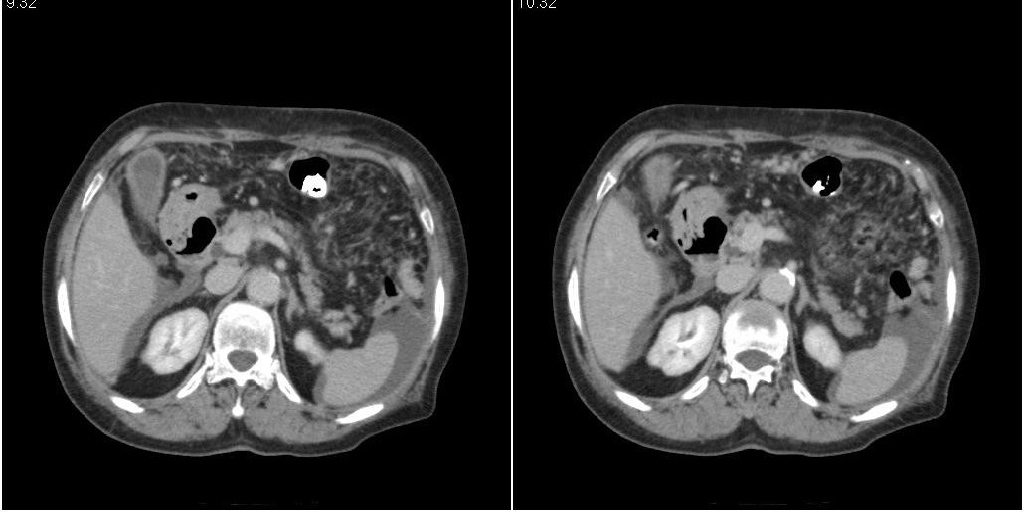

标题: CT24555:82岁女性,因为反复胸腹部积液进行CT检查,结果如下 [打印本页]

标题: CT24555:82岁女性,因为反复胸腹部积液进行CT检查,结果如下

胆囊有问题么,是结石么?胆囊内异常密度平扫30hu左右,增强各期无变化。

胆囊炎,胆结石,胆囊窝积液,胸腹水。

胆囊内稍高密度影,无强化,胆囊壁增厚,周围见低密度影,右侧膈肌角及脾周水样密度,支持胆囊泥沙样结石,胆囊炎、胆囊窝积液,胸腹水。

1)胆囊炎,胆结石;胆囊新生物待排。2)胆囊窝积液。3)腹水。4)右侧少量胸腔积液。